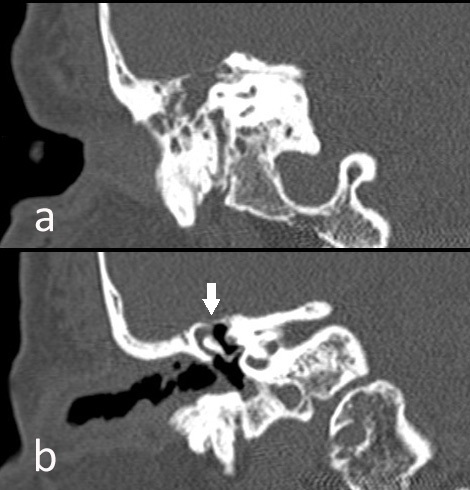

Presentamos imágenes de una paciente de 65 años en estudio por otalgia derecha con pérdida completa de la audición tras proceso gripal, con implante de tubo de drenaje transtimpánico. Posteriormente, inició otorrea abundante de líquido transparente, instaurándose tratamiento antibiótico ante la posibilidad de fuga de LCR. Mediante TC craneal se identificó una ocupación del oído medio, espacio de Prussak y receso hipotimpánico, con erosión del scotum y del tegmen timpani por probable colesteatoma (figura 1b, flecha). La exploración neurológica no demostró afectación meníngea, realizándose una cisternogammagrafía isotópica con 111In-DTPA ante la persistencia de la otorrea y sospecha de fístula de LCR, presentando actividad intensa del radiofármaco en oído derecho y en todos los tapones óticos (figura 2A, flecha). Una RNM cerebral posterior no mostró signos de encefalocele ni meningocele (figura 2B, flecha). Tras la confirmación de la existencia de fuga de LCR se instaló un drenaje externo lumbar conectado a circuito de depósito hermético y estéril, cediendo la otorrea, sin requerirse intervención quirúrgica.